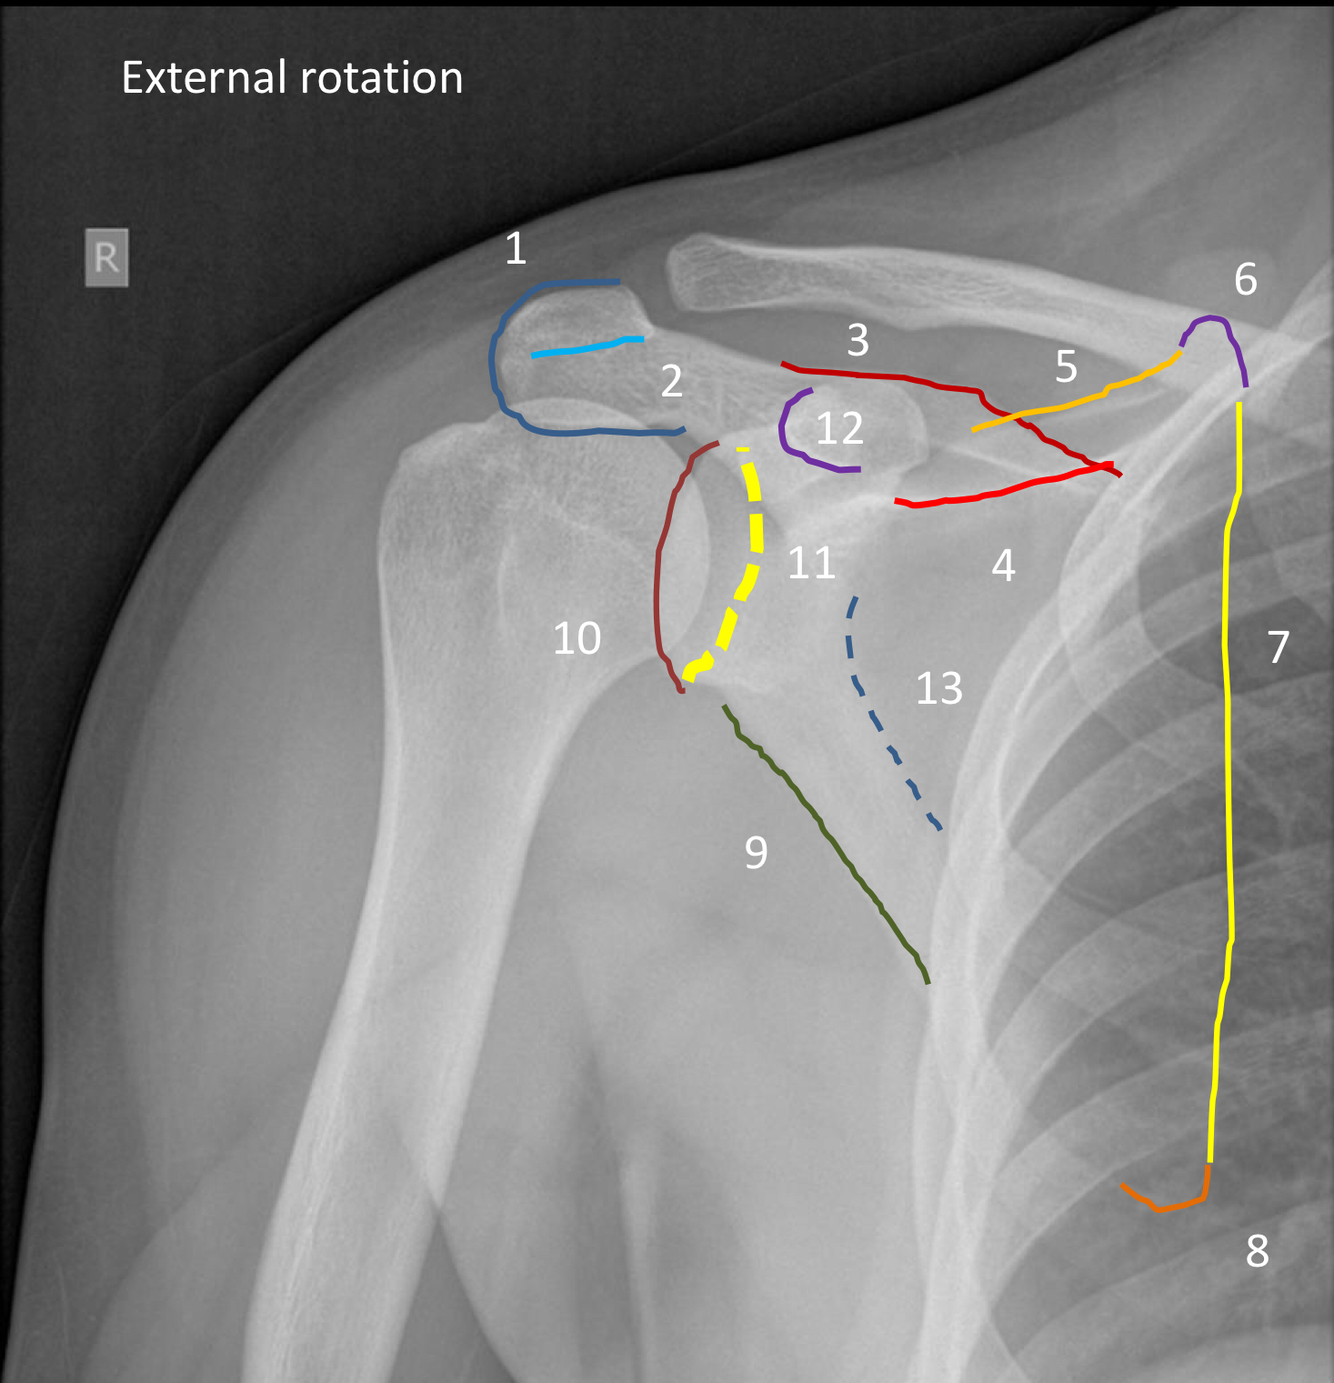

What view is this?

AP shoulder with internal rotation

What is the red arrow pointing to?

lesser tuberosity of the humerus (will be medial and in profile with internal rotation)

What is the blue area outlinging?

greater tuberosity of the humerus (will be superimposed with internal rotation)

1?

acromion

2?

inferior margin of acromion process

3 (dark red line)?

superior margin of the spine of scapula

4 (light red line)?

base of spine of scapula

5?

superior angle of scapula

6?